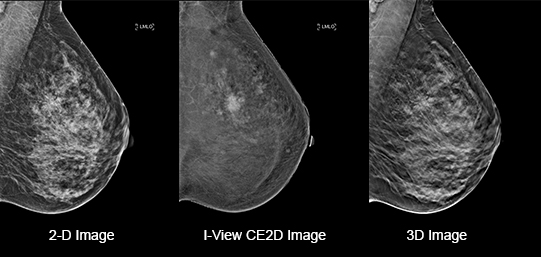

Eliminates Structural Background

Acquire a pair of high- and low-energy images in rapid succession. This allows for regions of abnormal blood flow to be displayed by subtracting the background breast parenchyma.

Contrast-enhanced mammography enhances visualization and may uncover hidden abnormalities – a crucial factor in reducing missed and or underdiagnosed cancers.